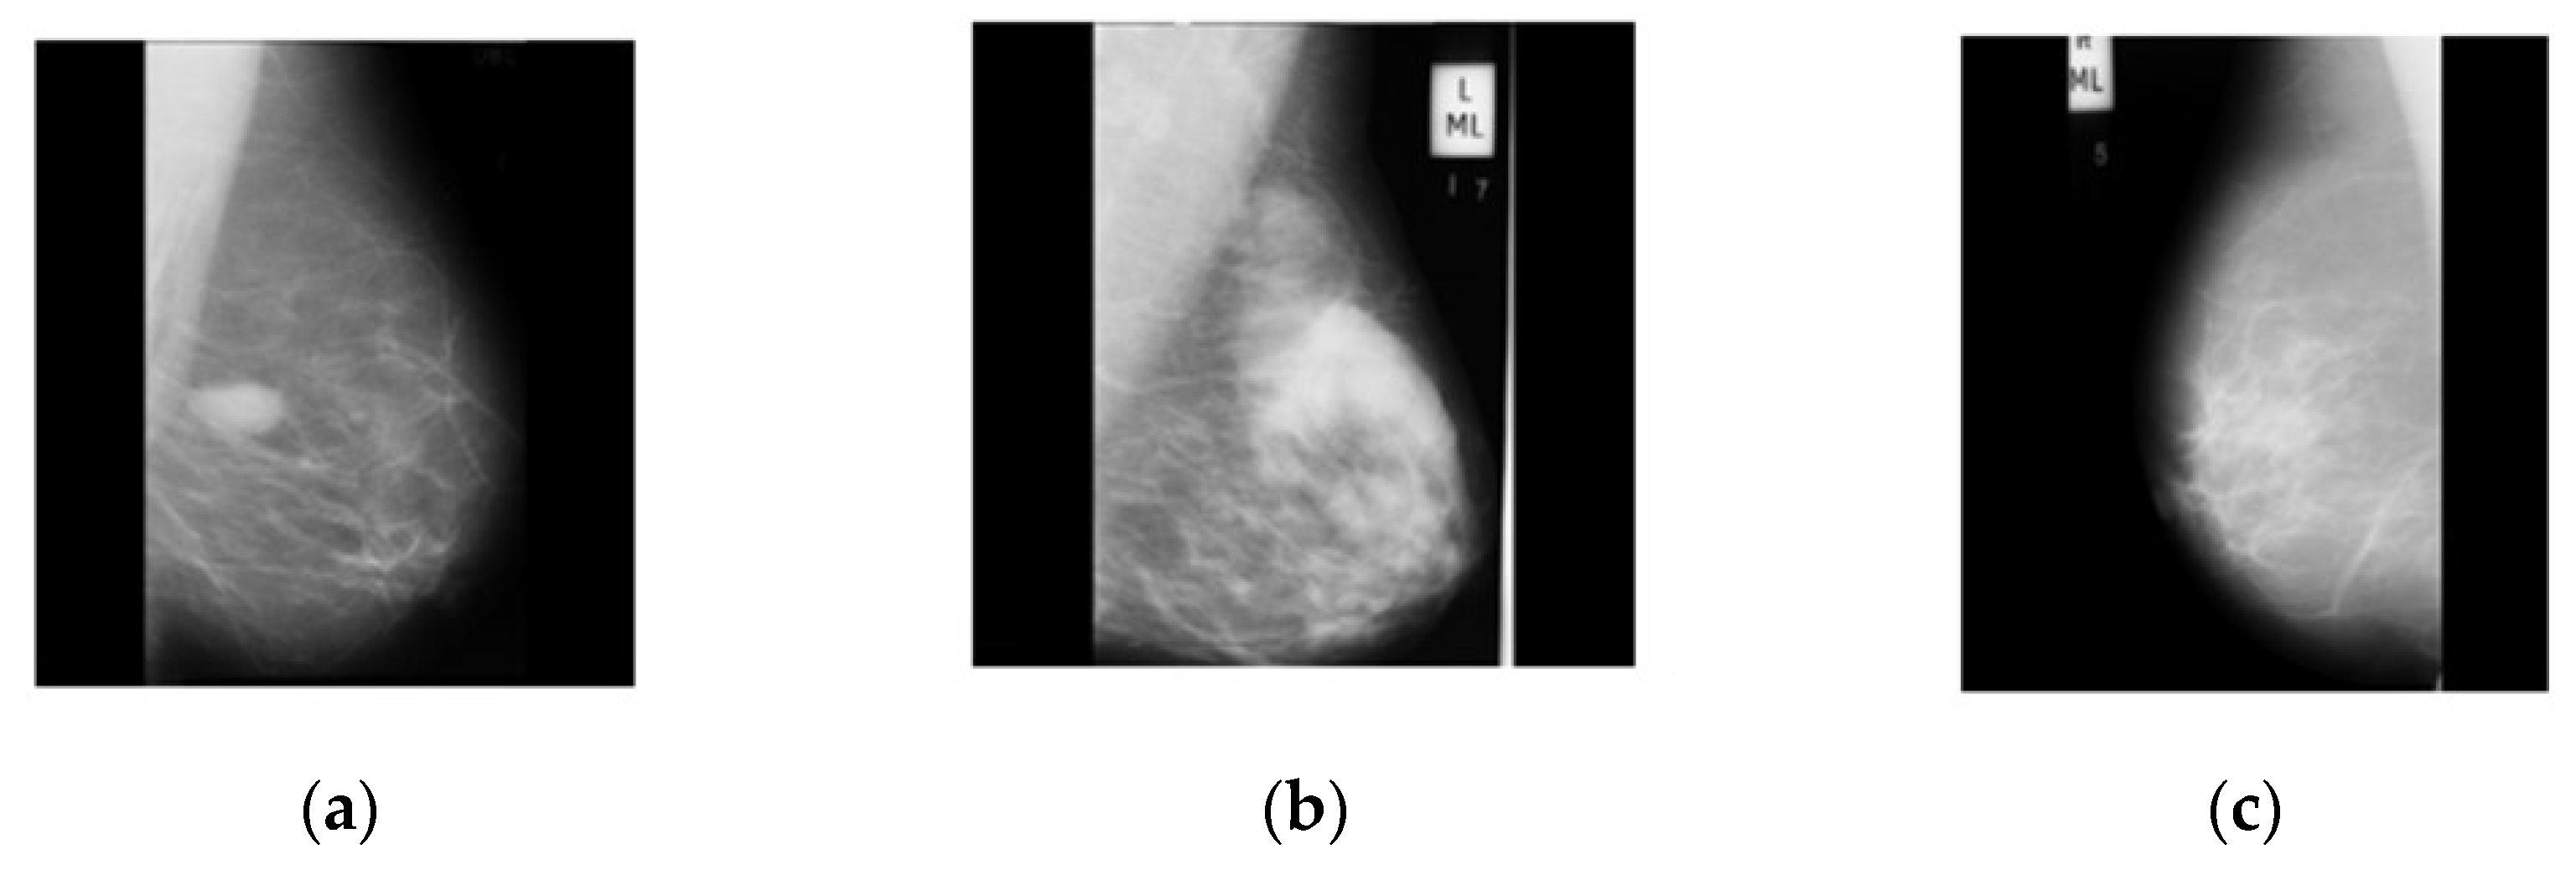

2.1. Dataset Collection

2.2. Dataset Augmentation

2.3. Contrast Enhancement